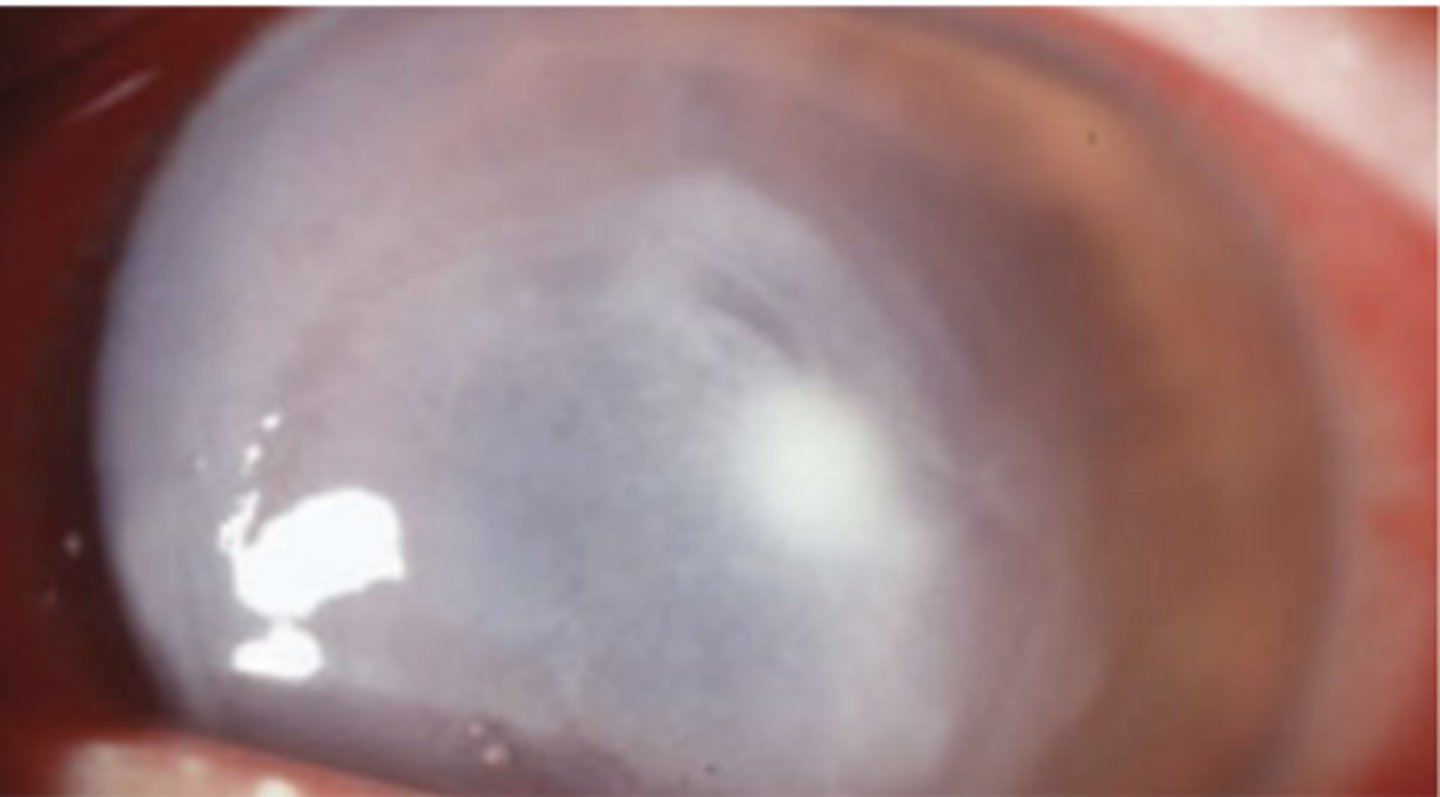

Full thickness epithelial loss with stromal necrosis and inflammation

What does a corneal ulcer look like?

Central and paracentral

Where is a corneal ulcer typically located (and familiarize yourself with scaling pictured)